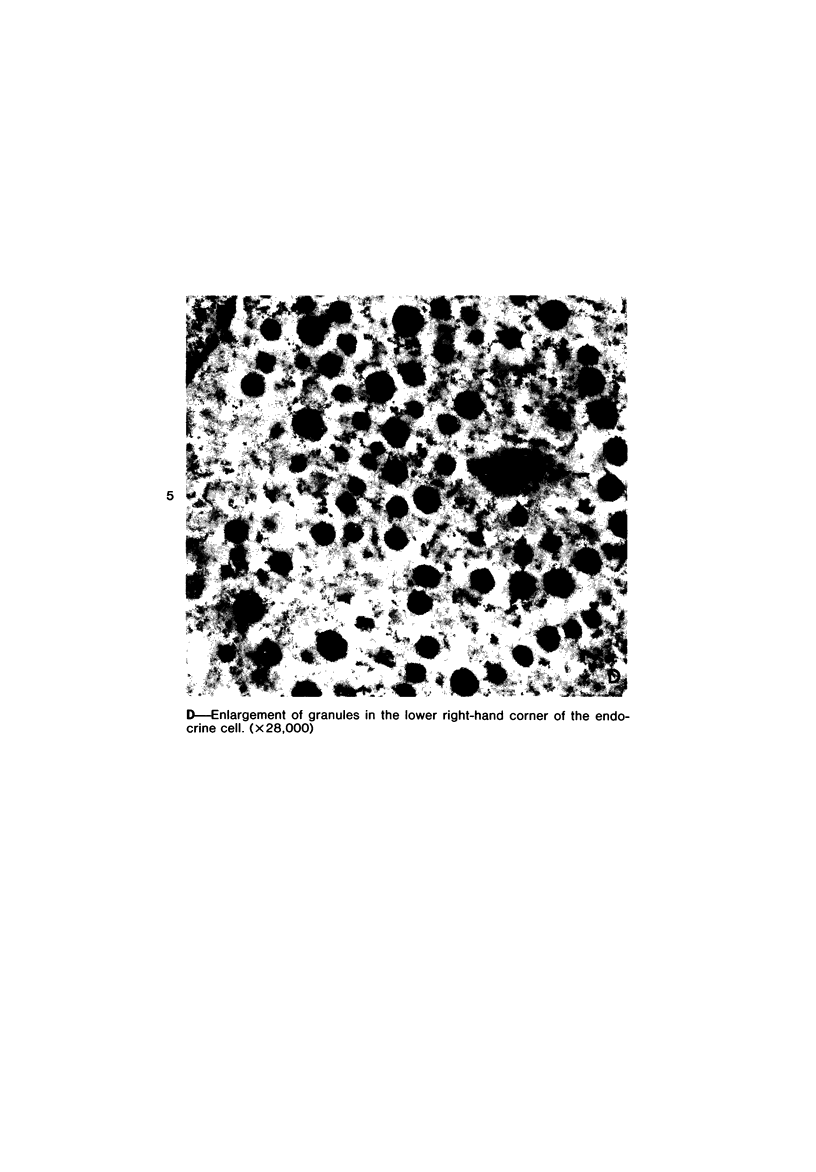

Images in this article